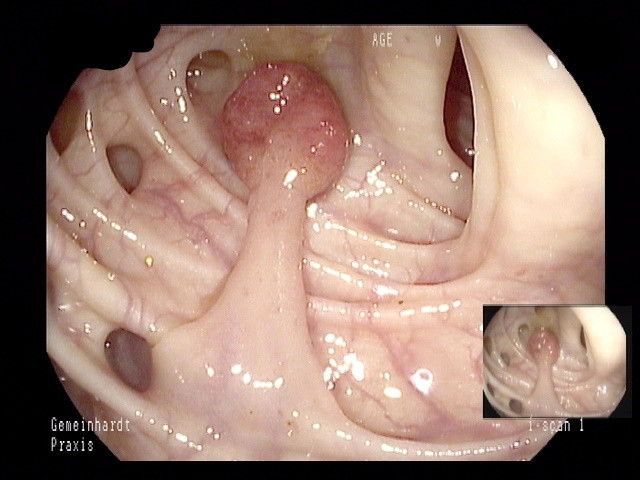

Besonders hervorzuheben ist der Stellenwert der Darmspieglung als Vorsorgeuntersuchung zur Verhinderung von Darmkrebs. Diese Untersuchung wird ab dem 50. (Männer) bzw. 55. Lebensjahr (Frauen) von den gesetzlichen Krankenkassen übernommen, ab dem 45. (Männer) bzw. 50. (Frauen) Lebensjahr wird bereits ein jährlicher Stuhltest bezahlt. Immer noch erkranken jährlich etwa 75.000 Menschen in Deutschland an Darmkrebs, 25.000 sterben daran. Durch rechtzeitige Vorsorgeuntersuchungen lässt sich Darmkrebs fast immer verhindern, da hierbei gutartige Vorstufen des Darmkrebses (Polypen) leicht erkannt und sicher entfernt werden können.

Darüber hinaus besteht die Möglichkeit, dass die Untersuchung mit Unterstützung durch künstliche Intelligenz (KI) durchgeführt wird. Die KI ersetzt dabei nicht den Untersucher, sondern unterstützt ihn, quasi wie eine "zweites digitales Augenpaar" bei der Suche nach Polypen. Während der Untersuchung wird das Live-Bild permanent mit einer riesigen, ständig wachsenden Datenbank verglichen und auf suspekte Befunde gescreent. Wird ein suspekter Befund entdeckt, wird der Untersucher optisch und akkustisch darauf hingewiesen und kann sich die Stelle gezielt ansehen und diese wenn nötig entfernen. Mehrere Studien konnten inzwischen zeigen, dass die Adenomdetektionsrate (ADR) als maßgebliches Maß der Untersuchungsqualität signifikant gesteigert werden kann, woraus eine höhere Untersuchungsqualität für Sie als Patient resultiert.